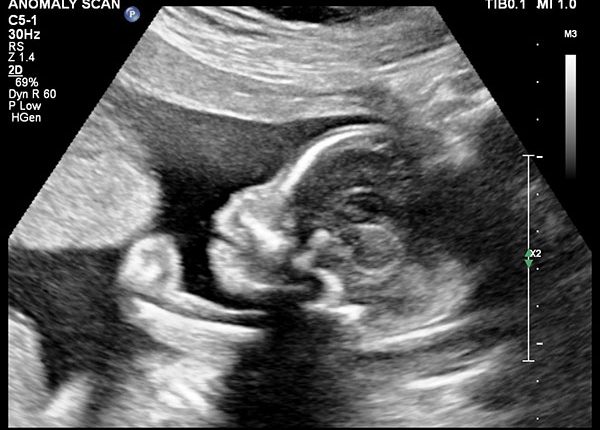

سونوگرافی آنومالی یکی از انواع سونوگرافی های مهم دوران بارداری است که به نام غربالگری آنومالی نیز شناخته می شود.

این سونوگرافی معمولا در هفته 20 بارداری انجام می شود اما می توان آن را در بازه ی زمانی هفته 18 تا 20 نیز انجام داد.

در این سونوگرافی، جنین، جفت، روند رشد جنین و وضعیت رحم مادر کامل بررسی می شود. برخی از مادران فکر می کنند که این سونوگرافی برای تعیین جنسیت نوزاد انجام می شود، درست است که پزشک در این سونو می تواند دختر یا پسر بودن جنین یا جنین ها را به شما بگوید، اما هدف اصلی این سونوگرافی تشخیص مسایل مهم تر وضعیت جنین است.

یکی از جذابیت های این سونوگرافی این است که شما می توانید اعضای بدن فرزند خود را مشاهده کنید. رنگ های سفید در عکس سونوگرافی، نشان دهنده ی استخوان های بدن جنین شما است.